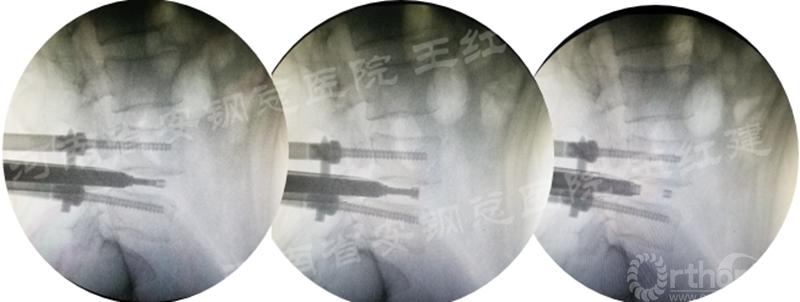

三、通道技术进行植骨、融合

应用通道技术进行植入融合时,首先要更换工作套管,通过枪钳、抓钳的应用处理椎间盘,接着进行自体骨或同种异体骨及cage植入,并通过C臂透视确定试模型号放置融合器,最终完成植骨融合。

确定融合器位置

四、经皮螺钉技术固定

在固定的步骤可以先期进行经皮螺钉置入,再进行融合器的置入,进而实现充分固定。

手术步骤:先期经皮螺钉置入、再进行融合器的置入